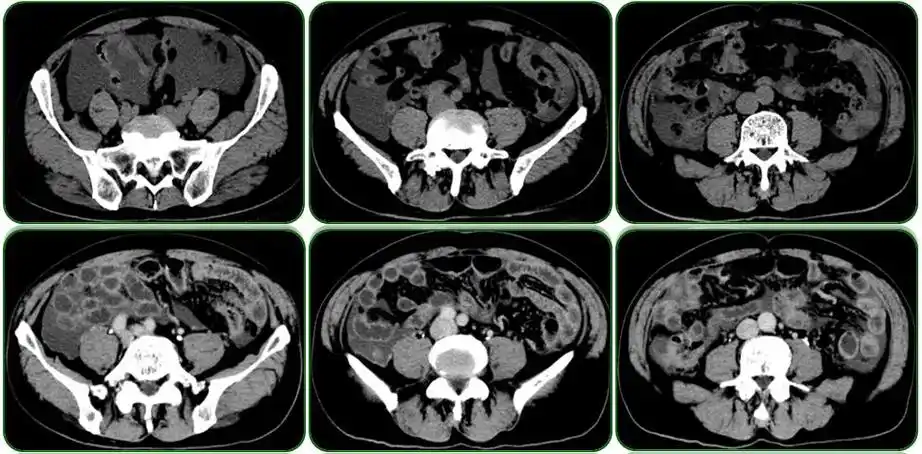

3个病例8副图带你读懂腹水

腹腔包裹性积液?

【讨论】大量盆腹腔积液,探讨病因81579

手术后第 天 ct 检查提示大量腹水